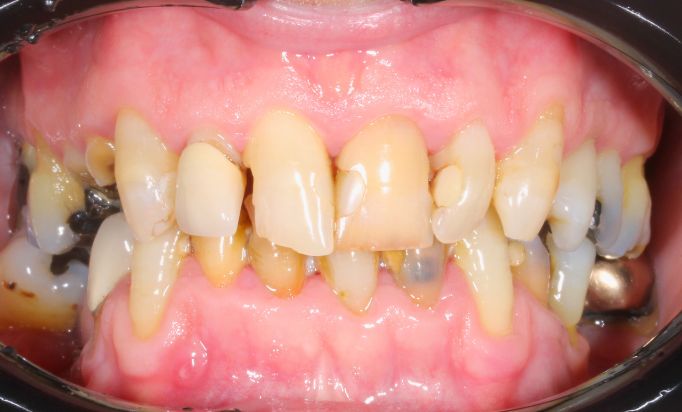

Cosmetic Dentistry

Improving smiles naturally

Helping you prevent dental issues with regular check-ups.

Dental Implants

Rebuild your smile, naturally

Achieve a seamless, natural-looking smile with dental implants.